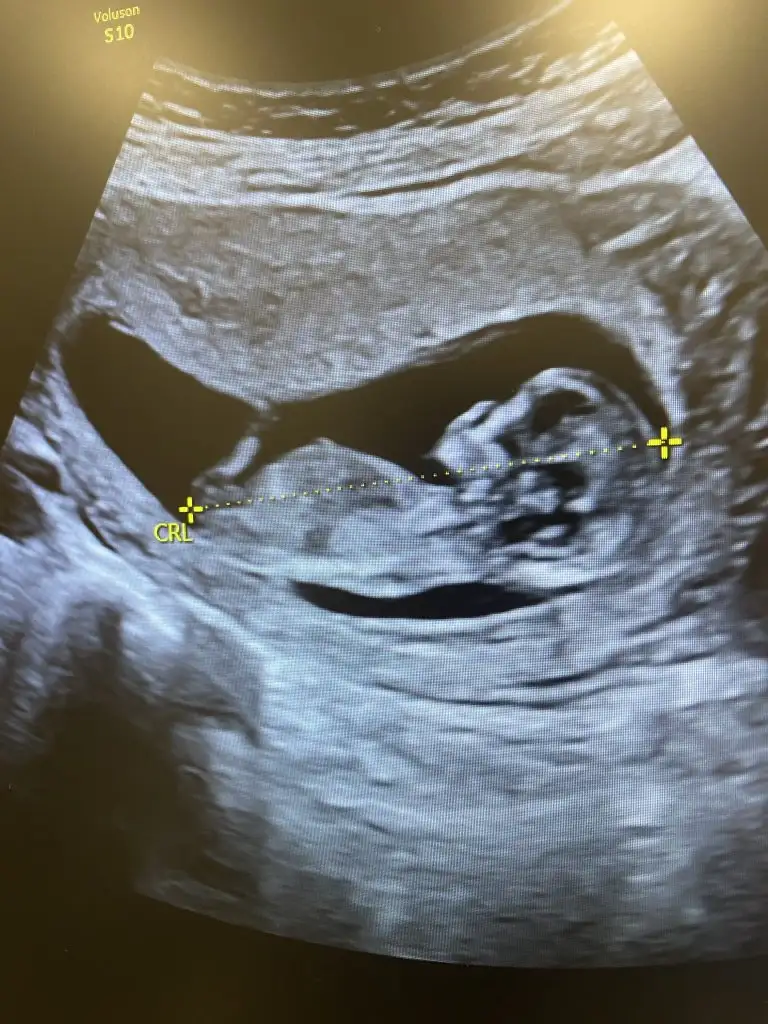

Sizin minik baya utangaçMerhaba kızlar bugün 12+6 olduk bizim minik inatla göstermedi cinsiyetini sonda da iki eliyle bacak arasını kapattı resmen bir sonra ki kontrolüme daha çok var meraktan çatlicam resmen tahminlerinizi alabilir miyim lütfen

Teyzeleri alınıyoruz ama kimse yorum yapmayacak mıAnlayan annelerrrrr biz de çok merak ediyoruz 12+2 sizce cinsiyeti ne ?

Eki Görüntüle 3450798